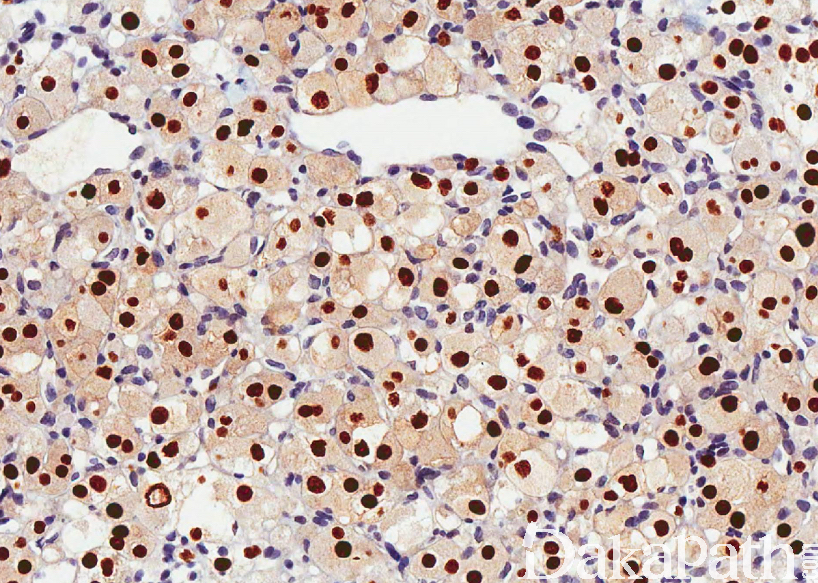

低倍镜下见肿瘤细胞呈“器官样"或“腺泡状”排列,腺泡之间为裂隙状或血窦样毛细血管网;

瘤细胞体积较大,圆形或多边形,边界清楚,胞质丰富,含嗜伊红色颗粒;核大,染色质细致或呈空泡状.可见明显的核仁,核分裂像较少;

大多数病例胞质内可见 PAS 阳性的针状或棒状结晶物,耐淀粉酶消化;

TFE3 弥漫强阳性(核表达),部分病例还可表达 desmin、MSA 和 MyoD1(胞质染色),不表达 myogenin、AE1/AE3. EMA、CgA、SYN 和 NF,HMB45,MELAN-A,S100 等。